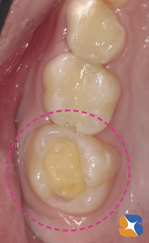

小学生。夏休み終盤の8/29。主訴は、上の奥歯「学校検診で虫歯が見つかった。最近、甘い物を食べると痛い。遠方のため、早く終わらせたい」でした。

更に「以前、下の奥歯に銀歯を詰めた時、しばらく痛みが続いたので、今回は痛みの少ない(素材の)詰め物でお願いします」が親御様からの要望でした。その結果、セラミックの詰め物を装着することに決まりました。

セラミックなら金属と異なり、熱が伝わりにくいため、冷たさや熱さに対して痛みが少ないからです。また、院内でDr自身が製作するため、噛み合わせを考慮したセラミックの詰め物が、治療開始から2時間後には治療が終わっていることもメリットの一つです。